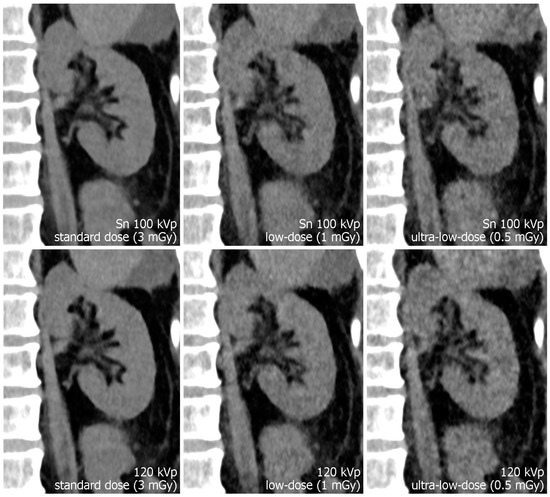

Figure 3.

Para-coronal images displaying the left kidney. The renal pelvis is not dilated but pelvic structures remain assessable even in ultra-low-dose images. Note the increased noise in the 120 kVp ultra-low-dose study compared to the dose-matched protocol with tin filtration.